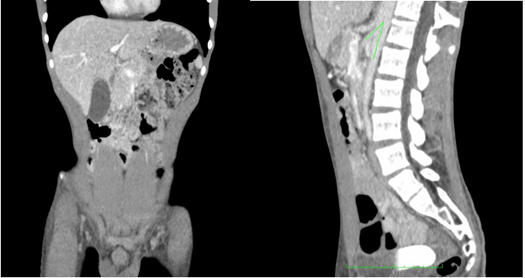

El paciente tuvo una mejoría clínica y anímica evidente, sin vómito ni dolor abdominal y desapareció la ictericia. Un mes después se decidió tomar una TC de control, en la cual se observaba desaparición del aire en la porta y retorno del estómago a su tamaño normal, con desaparición de la neumatosis en la pared; había aumento del ángulo aorto-mesentérico a 28,9 grados en el corte sagital, con paso del medio de contraste al íleon distal y aumento de la distancia aorto-mesentérica a 5,2 mm en el corte axial (Figura 2).

Figura 2. Tomografía computarizada de abdomen después de un mes de tratamiento con soporte nutricional, en la que se observa que el estómago ha retornado a su tamaño usual, no hay aire en la vena porta y el ángulo aorto-mesentérico mide 28,9 grados.